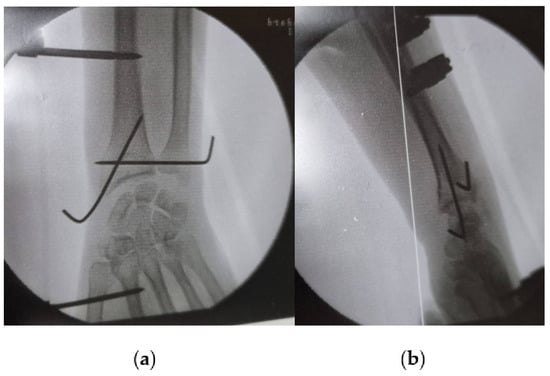

Conventional radiography is valuable for evaluating joint instability and excluding other potential causes of wrist pain, such as fractures or arthritis [12]. However, it primarily focuses on bone imaging and may not fully assess soft tissue structures, although sometimes, DRUJ injuries can be seen via simple X-ray, as illustrated in Figure 1, which shows a forearm fracture with an associated DRUJ injury (there is an increased radioulnar distance, as well as a dorsal dislocation of the ulnar head) (Figure 2). Dynamic joint motion cannot be evaluated with static radiographic images. In cases of suspected ligamentous injuries or more complex DRUJ pathology, additional imaging modalities like MRI or CT may be necessary for a comprehensive assessment [25,26].

Figure 2. Forearm fracture with radiographic evidence indicating distal radioulnar joint (DRUJ) injury: (a) antero-posterior view (increased radioulnar space); (b) lateral view (dorsal dislocation of the ulnar head).